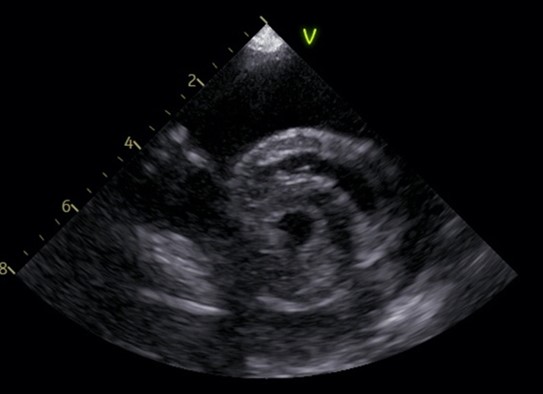

症例は、心膜内に液体が貯留し、心臓の動きを圧迫する所謂“心タンポナーデ”を呈していました(写真1)。心嚢水抜去を行っても再度貯留してしまうことから、症状緩和を目的に心膜切開術を実施したところ、左心耳に腫瘍性病変を発見、切除することができました(写真2)。

(写真1 心嚢水貯留時の心臓超音波画像)